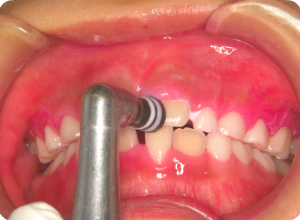

②磨き残しや汚れなどを、ブラシとラバーカップを使って落としていきます。

キレイになりました。